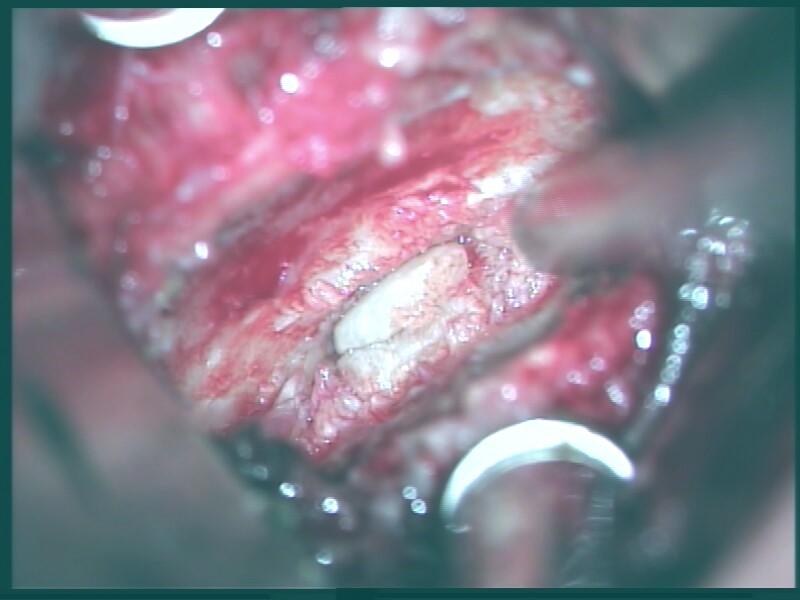

Bei der Operation, welche unter Vollnarkose durchgeführt wird, wird ein ca. 4 cm langer, kleiner Schnitt im Bereich der rechten Halsseite angelegt und die Wirbelsäule dargestellt. Unter dem Operationsmikroskop wird die Bandscheibe ausgeräumt und vorhandene knöcherne Einengungen mit Diamantfräsen und feinen, speziellen Stanzen abgetragen. Danach wird die Bandscheibe durch einen Kunststoff- (PEEK) Cage oder ein Titan-Implantat versteift. In speziellen Fällen kann eine Bandscheibenprothese Anwendung finden.